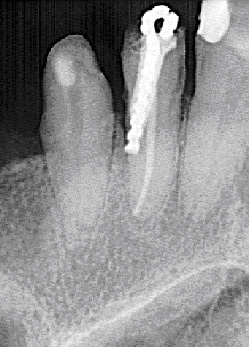

Nesta foto, você pode observar como o dente cuida do tratamento da pulpite usando o método resorcinol-formalina (amputação desvital):